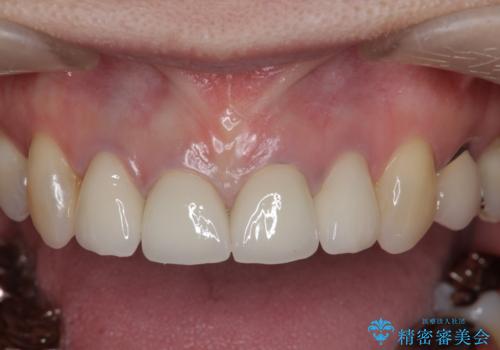

- 「黒ずみの前立つ前歯をやりかえ、きれいにしたい。」と希望され来院されました。

金属色の目立つ前装冠を除去し、発生していた小さな虫歯を丁寧に全て除去しジルコニアセラミッククラウンで審美的な前歯となるような治療を計画します。

金属を用いないジルコニアセラミッククラウンは透明感の再現性に優れ、審美性と自然な仕上がりの両立を期待することができます。